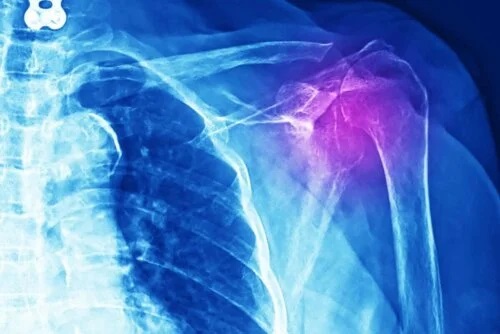

Simptomele și diagnosticul tendinitei umărului

Cel mai evident simptom al tendinitei umărului este inflamația și durerea.

Bolnavul poate avea o sensibilitate sporită atunci când mișcă și întinde un mușchi sau când exercită presiune asupra articulației. În plus, poate exista o lipsă de putere, deoarece inflamația, durerea și lipsa de forță care caracterizează tendinita umărului limitează capacitatea persoanei de a-și desfășura activitățile zilnice.

Medicii trebuie să facă diferite teste pentru a diagnostica acest tip de leziune. Poate fi vorba despre radiografie, ultrasunete, RMN sau tomografie axială computerizată (scanare CT). În plus, trebuie să existe un examen medical și un studiu detaliat al istoricului medical al pacientului.